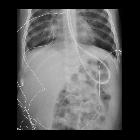

Young adult

who is coughing after feeding tube placement. Initial AXR (left) shows the tip of the feeding tube in the left mainstem bronchus. Subsequent AXR after feeding tube repositioning (right) shows the feeding tube tip to be in the fundus of the stomach.The diagnosis was feeding tube malfunction with the feeding tube tip in the left mainstem bronchus.